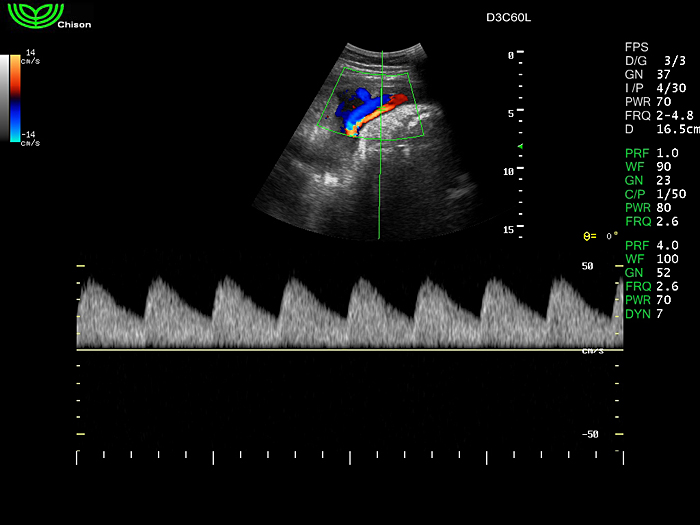

D3C60L 3.5МГц, конвексный.

2.0МГц - 5.8 МГц. Применения: абдомиальное обследование, акушерство, гинекология, обследование районной блокады нерва, осуществление и управление биопсией. |